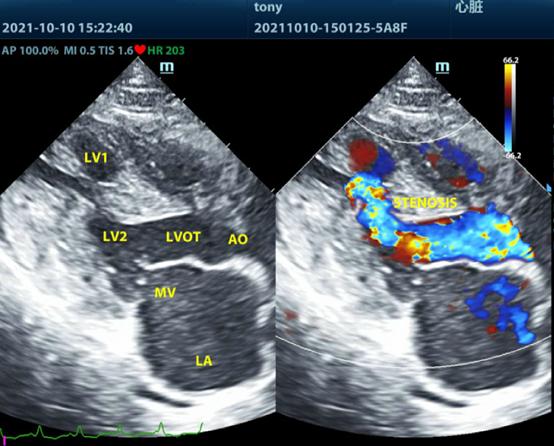

在刘传敦院长的职业生涯中,每一个疑难病例都是对其专业能力的深度淬炼。英国短毛猫Tony心源性肺水肿的成功救治,堪称他将深厚理论功底与丰富临床经验完美结合的典范案例。

面对Tony突发的心力衰竭复发并伴随严重气道阻塞的危急病情,刘传敦院长凭借敏锐的专业判断,果断采用当时国内尚属罕见的呼吸机正压通气治疗方案。这一决策不仅需要准确把握治疗时机,更要求医生具备扎实的专业底蕴和丰富的临床经验。在治疗过程中,他通过深度镇静与气管插管的精准配合,有效清除了气道阻塞物,并借助呼吸机正压通气技术成功克服了气道阻力,为改善心功能赢得了宝贵时间。

瑞派心脏专科组是由一群成熟的、朝气蓬勃的、为了梦想而努力拼搏的优秀兽医师所组成,主要有刘传敦、罗庚、李静、李丽、汤新维等众多心脏专科兽医师,他们在犬猫常见获得性和先天性心脏疾病的诊断、治疗上有着丰富的经验,能熟练地使用心电图机和彩色多普勒超声波诊断仪等仪器检查和辅助心脏疾病的诊断、治疗监测和预后。

擅长心血管、内科(呼吸/肝胆/肾/内分泌疾病等)疾病诊治与管理以及影像学诊断(超声)。